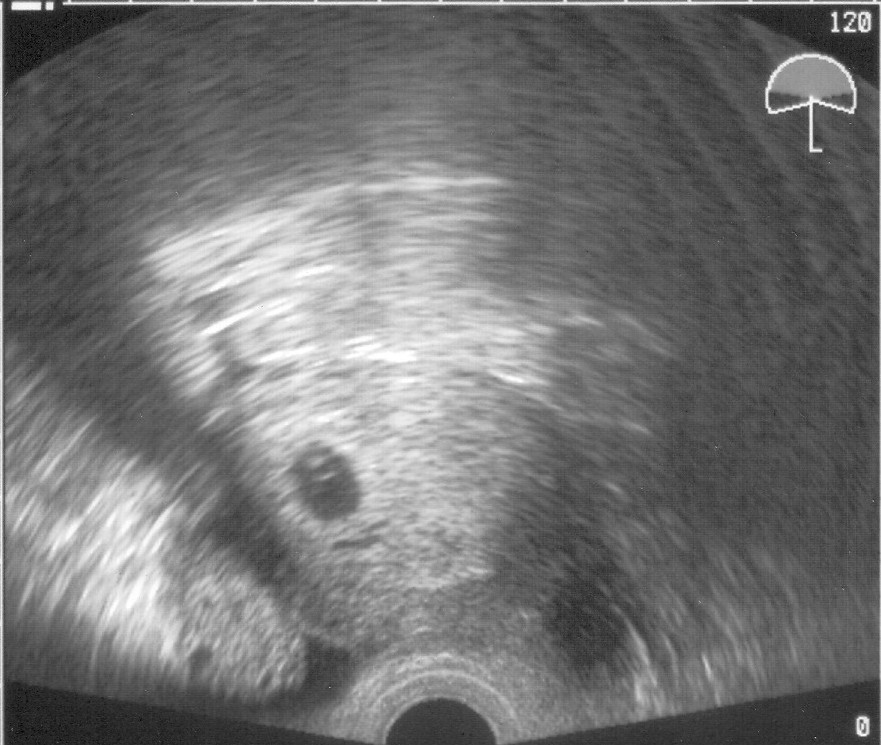

melde mich gehorsamst aus England zurück, haben alles gut überstanden. Waren gestern nochmal beim US und haben Euch was zum Mutmachen mitgebracht (s.u.)

US 2007-11-01 - 5+6 klein.jpg

Bild Bild

KatZ-LE Meinen Glückwunsch!! *knuddel* Hoffentlich können wir hier bald auch alle so ein schönes US-Bildchen vorweisen! :knuddel:

sorry, tue mich noch schwer mit der Technik. Keine Ahnung wie KatZ-Le sogar ein US-Foto von der Qualität hier reinbringt :oops: